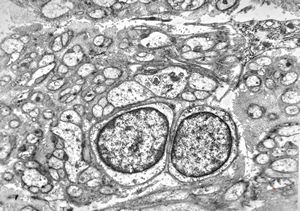

M, 11y. | mycosis fungoides v.s. - cerebriform nucleus of Sézary cell

F, 57y. | mycosis fungoides … cerebriform nucleus of Sézary cell

F, 37y. | mycosis fungoides … cerebriform nucleus of Sézary cell

M, 70y. | mycosis fungoides - Sézary cell

M, 70y. | mycosis fungoides - Sézary cell